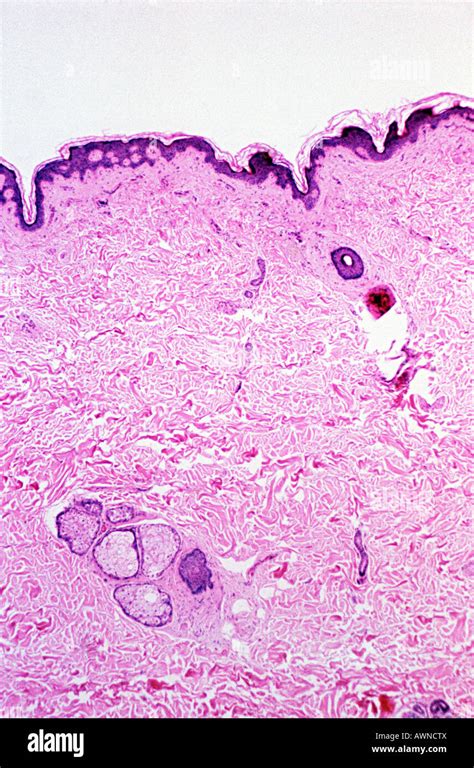

È importante sottolineare che la melatonina non è prodotta esclusivamente dalla ghiandola pineale, ma anche da numerosi altri organi, tra cui la cute stessa. A livello cutaneo, la melatonina è implicata in aspetti fisiologici che riguardano i maggiori compartimenti della pelle: epidermide, derma e annessi, comprese le strutture pilifere. Il "sistema melatoninergico cutaneo" rappresenta il complesso di vie metaboliche e recettori attraverso i quali la pelle sintetizza, metabolizza e utilizza la melatonina e i suoi derivati.

La melatonina interagisce con specifici recettori di membrana presenti sulla superficie delle cellule cutanee, come i cheratinociti e i melanociti. Questi recettori sono coinvolti nella regolazione di numerosi processi cellulari, inclusa la proliferazione e la differenziazione cellulare.